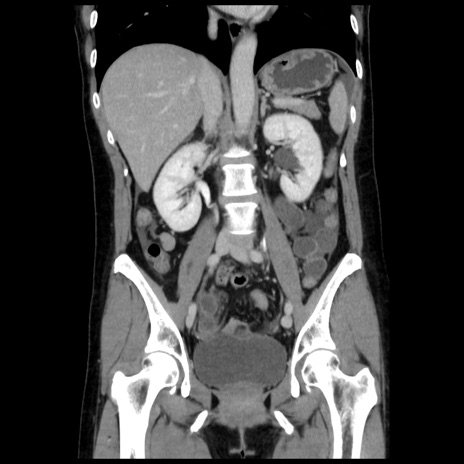

症例10(冠状断像)

【症例】 50歳代女性

【主訴】 腹痛

【現病歴】前日生レバーを食べた。今朝に排便あり。 昼前に突然発症の腹痛を生じ、当院救急外来を受診した。

【既往歴】 子宮筋腫にてで子宮全摘後

【身体所見】 意識清明、腹部:平坦、軟、下腹部やや左を中心に圧痛・反跳痛あり、筋性防御あり

【データ】WBC 7800、CRP 0.07